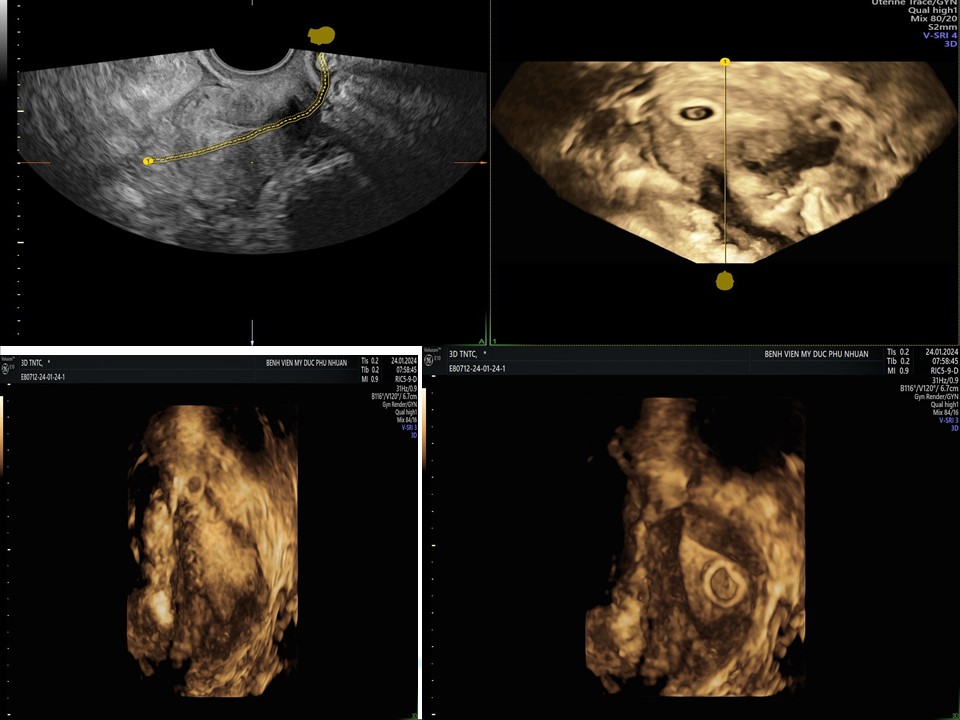

Siêu âm đánh giá khả năng sống của thai giai đoạn sớm

BS. CKI Phạm Thị Phương Anh - BV Mỹ Đức